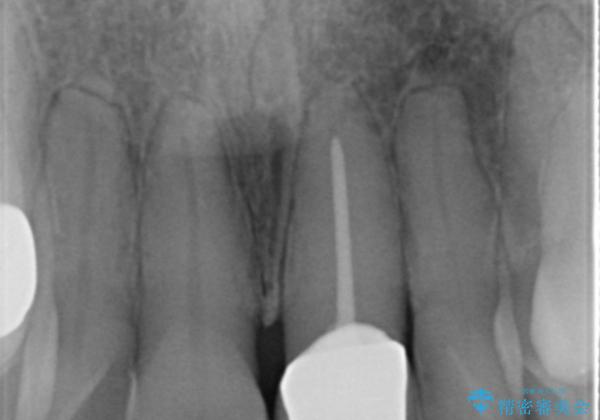

神経の治療をした歯は時間の経過と共に色調の変化が見られます。

このような際、ジルコニアクラウンを装着することで審美性の改善を達成することができます。